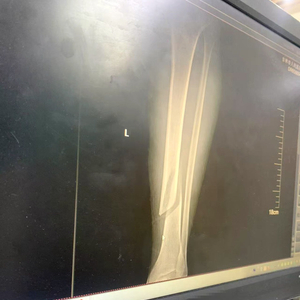

落地后,他感到左腿钻心疼痛。其身后有两名滑友发现情况后赶来,帮助拨打了滑雪度假区的急救电话。很快,救援人员赶到了事发现场,用担架将其送到了滑雪度假区的医务室。经值班医生检查和做出相应处理后,他被送到了吉林市人民医院,医学检查显示,其左腿胫腓骨骨折。